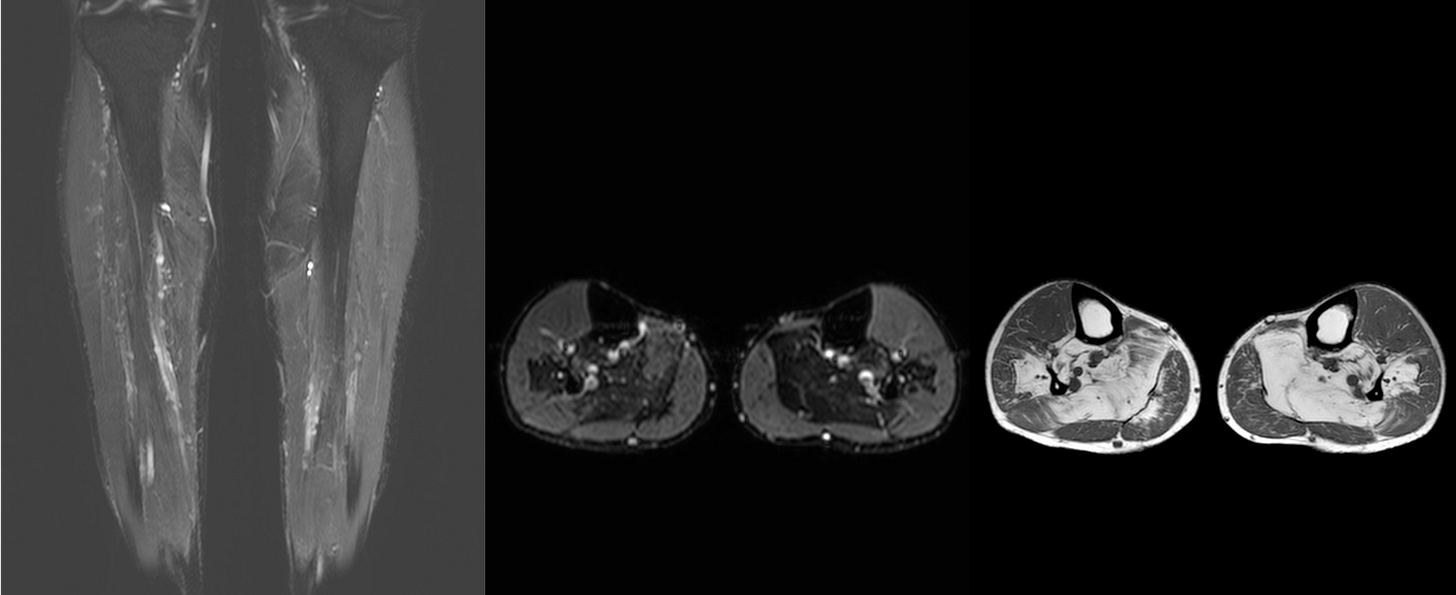

Case 61: Dermatomyositis and the Myositis Protocol MRI

55-years old with dermatomyositis

55-years old diagnosed to have dermatomyositis, referred for a myositis protocol MRI.

The video (published earlier as COD 021) discusses the case, the myositis protocol MRI and other cases of dermatomyositis.